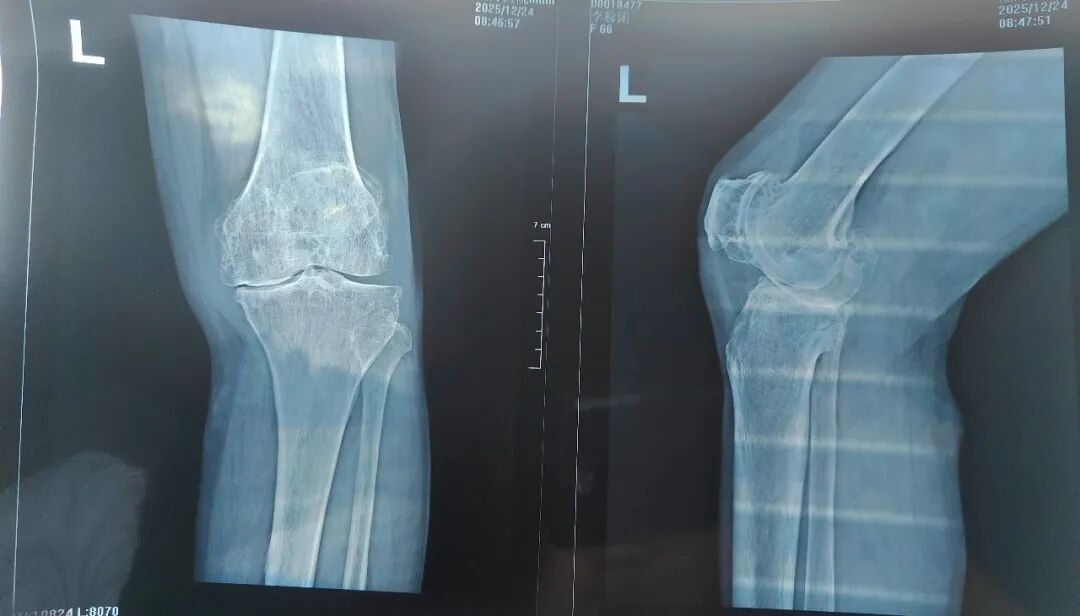

李女士的双膝疼痛已困扰她30余年,尤其是左膝,疼痛持续加重,伴随膝内翻畸形,日常行走都十分困难。多年来,她辗转多家医院进行保守治疗,但效果不佳,生活质量备受影响。入院检查显示,患者不仅患有双侧膝关节骨性关节炎,还合并高血压、甲状腺功能减退症、慢性支气管炎等多种基础疾病,这为手术带来了极高的风险与挑战。

在充分的术前准备基础上,骨科蔡志荣主任带领团队,为李女士实施了左侧全膝关节置换术。团队凭借精湛的操作技术,精准完成了假体植入与软组织平衡,术中出血量仅30毫升,无需输血,患者生命体征平稳。得益于“快速康复外科”理念的应用,李女士在术后第二天就能在助行器辅助下站立并行走。恢复速度远超传统关节置换术后的康复进程,患者及家属对治疗效果赞不绝口。